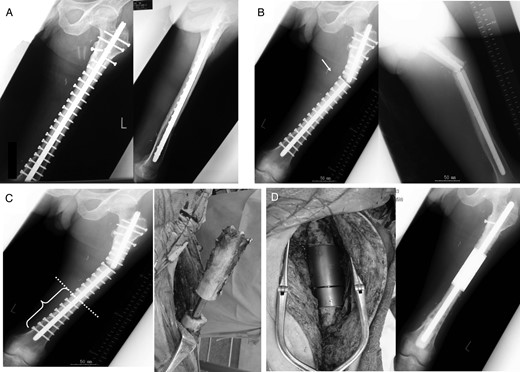

Case 1: A 61-year-old male was treated at the age of 54 for primary soft-tissue sarcoma of the thigh which invaded the femur (Fig. 1A–D). Wide en bloc resection of the tumor with involved femoral diaphysis, isolation of the tumor with involved bone, extracorporeal irradiation with 50 Gy as a single bolus dose to the isolated bone and reimplantation of the irradiated bone into the host with intramedullary nail were performed (Fig. 2A). At 74 months after primary surgery, graft bone fracture and intramedullary nail breakage occurred at the proximal diaphysis (Fig. 2B). Segmental intercalary resection, implant removal and reconstruction with custom-made intercalary prosthesis were performed (Fig. 2C and D). The best MSTS score was 20 of 30.

Radiographs showing extracorporeal irradiation after wide resection and stabilization with intramedullary nail (A). At 74 months after operation, radiograph showing fracture of graft bone with broken implant (B and C) and revision with intercalary endoprosthesis (D).